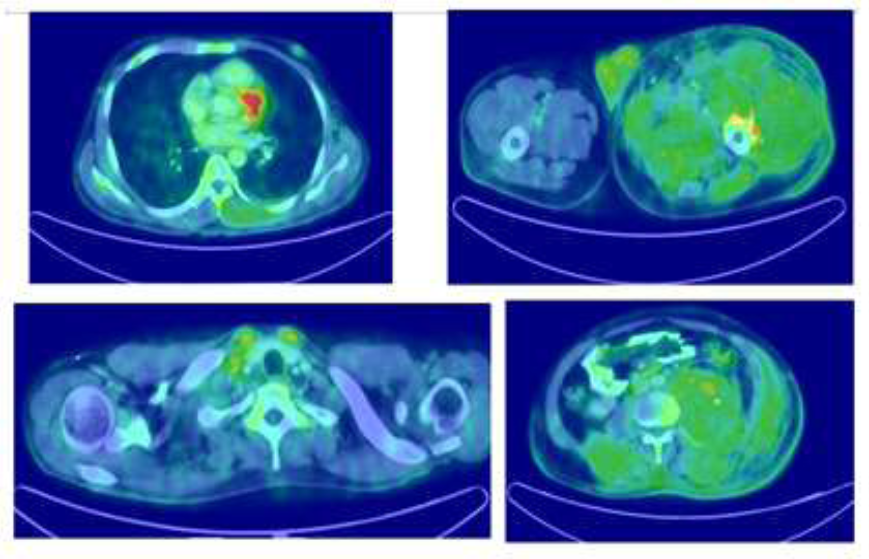

He underwent FDG PET CT which showed metabolically active diffuse edema and thickening involving the left thigh muscle with soft tissue thickening and stranding in the right upper medial chest wall and a nodule in the right lower outer quadrant of breast. (Figure 2).

Figure 2b: FDG PET CT showing involvement of the left thigh muscle and a nodule in

the right lower outer quadrant of breast